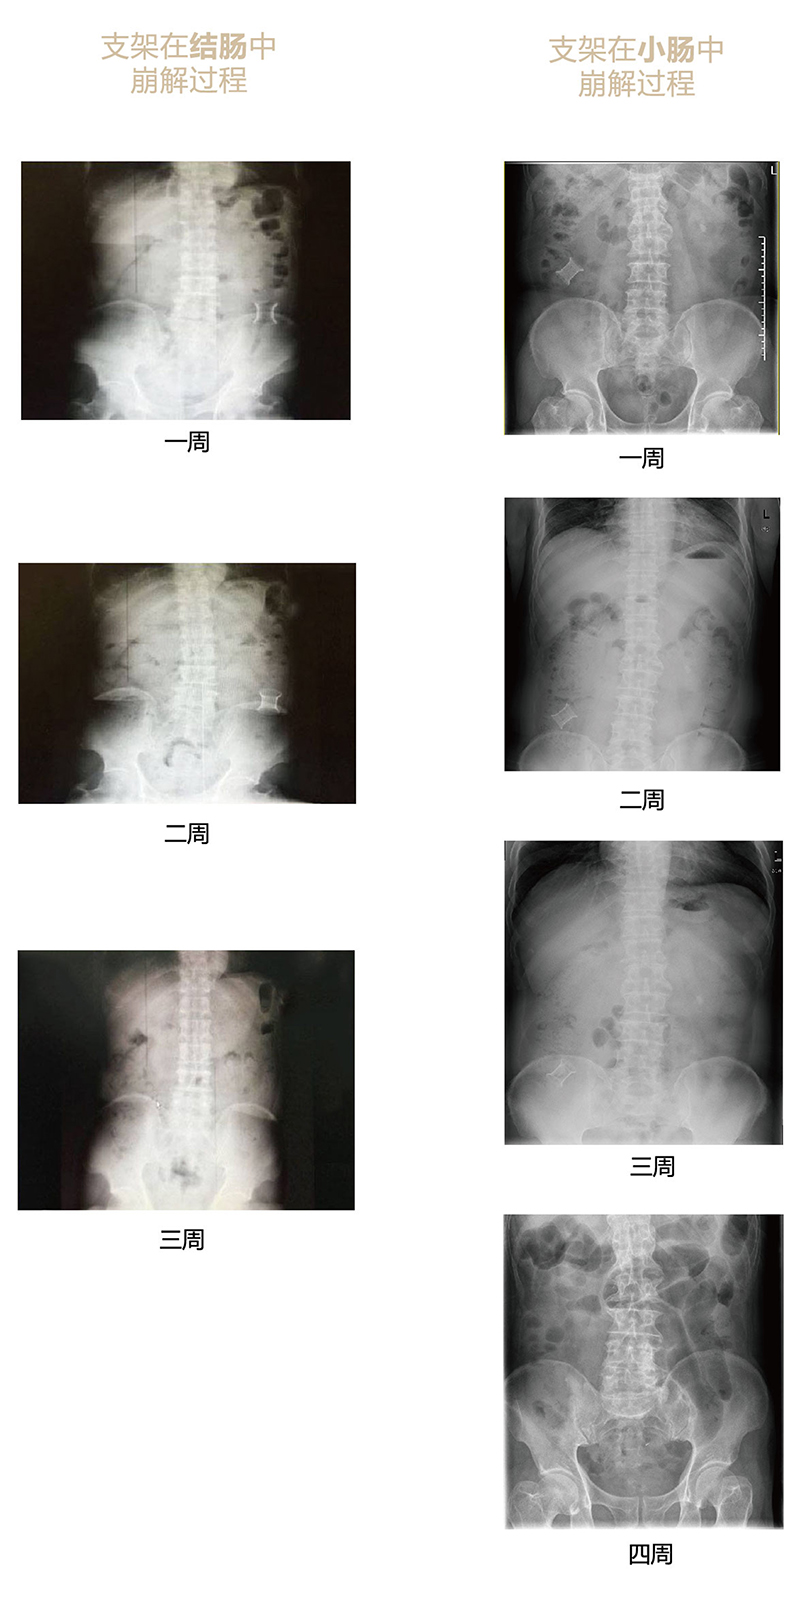

可崩解腸道吻合器由聚乙醇酸(PGA)與硫酸鋇按重量比7:1混合注塑制成,在X線下顯影,可動(dòng)態(tài)追蹤可崩解腸道吻合器(支架)在腸道內(nèi)崩解過程。

為解決該問題,蔡秀軍教授在“支架法空腔臟器吻合技術(shù)”的理念基礎(chǔ)上,又發(fā)明了“蔡氏腸轉(zhuǎn)流術(shù)”,這是一種應(yīng)用可崩解腸道吻合器HB型(可崩解腸轉(zhuǎn)流支架)(發(fā)明專利號(hào):201910794214.3),的支架法腸道轉(zhuǎn)流術(shù),此創(chuàng)新術(shù)式既能保護(hù)低位吻合口,更避免了回納術(shù)??杀澜饽c轉(zhuǎn)流支架在直腸癌根治術(shù)中植入遠(yuǎn)端回腸,可確保完全阻斷腸腔,用腸造瘺管在轉(zhuǎn)流支架近端行腸造瘺,起到完全轉(zhuǎn)流的作用。腸轉(zhuǎn)流支架在二至三周內(nèi)逐漸崩解,并在四周內(nèi)完全排出體外,恢復(fù)腸道通暢后拔除造瘺管,避免了傳統(tǒng)造口回納的二次手術(shù)。該創(chuàng)新術(shù)式具有方法簡單、吻合時(shí)間短、人體內(nèi)無異物永久殘留、不破壞吻合口粘膜下血管,并能預(yù)防吻合口漏、可避免人工肛門留置及二次手術(shù)、治療周期可縮短至二至四周、患者生理心理創(chuàng)傷顯著減少。